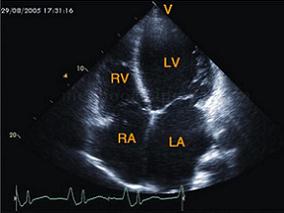

1小时条评论【病例2】 病史和相关检查 患者,男性,56岁。24小时前无诱因突发胸闷,局限于胸骨下端,伴冷汗,无放散,持续约1小时后缓解,无恶心呕吐。发现血压高10年,最高180/100mmHg。心电图:V1~V3病理性Q波,ST段抬高。血生化检查:LDH、CK升高。 超声图片 如图2‐1‐1...